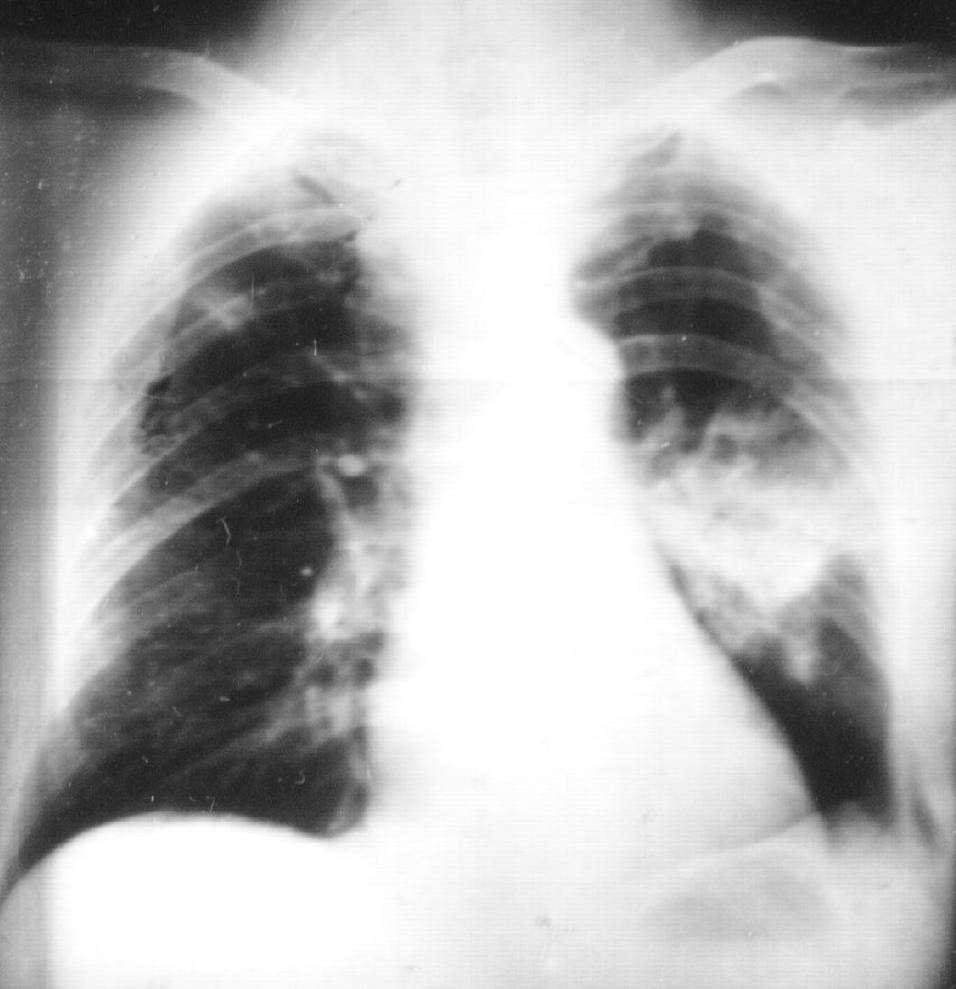

二、这是典型肺结核X线诊断特征:

目前的最新分类为:Ⅰ型: 原发综合征; Ⅱ型: 血行播散型; Ⅲ型: 继发性肺结核 (浸润性肺结核,空洞性肺结核,结核球,干酪样肺炎,纤维空洞型肺结核等); Ⅳ型: 结核性胸膜炎。

从影像学上,有可能表现为Ⅲ型继发性肺结核,也有可能更像原发综合征——有肺部淋巴结肿大、有肺内实质的浸润等等。

还有单一的结核球改变,看了影像后应不太会忘记。(卫星灶 2~4cm,多小于3cm)